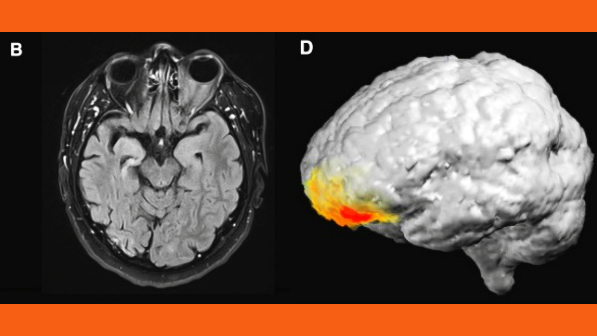

Further investigation revealed that the IED rate reductions occurred specifically in the subjects’ bilateral frontal cortices. Additionally, the team found evidence that emotional responses to Mozart’s music, as well as the musical structure of the sonata itself, may contribute to its therapeutic effect.